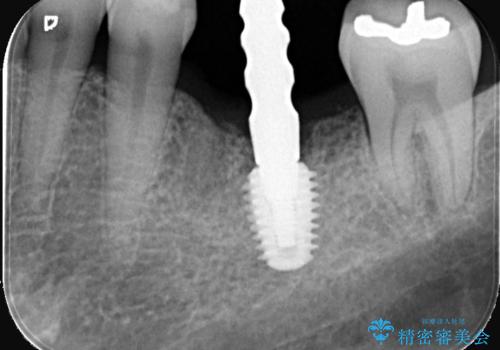

- レントゲン検査にて、根尖および側枝付近に骨の透過像が認められました。

さらに精査したところ、根のパーフォレーション(根に穴が開いてしまっている状態)が確認されたため、

患者様と相談のうえ、インプラントによる治療をご希望され治療を行いました。